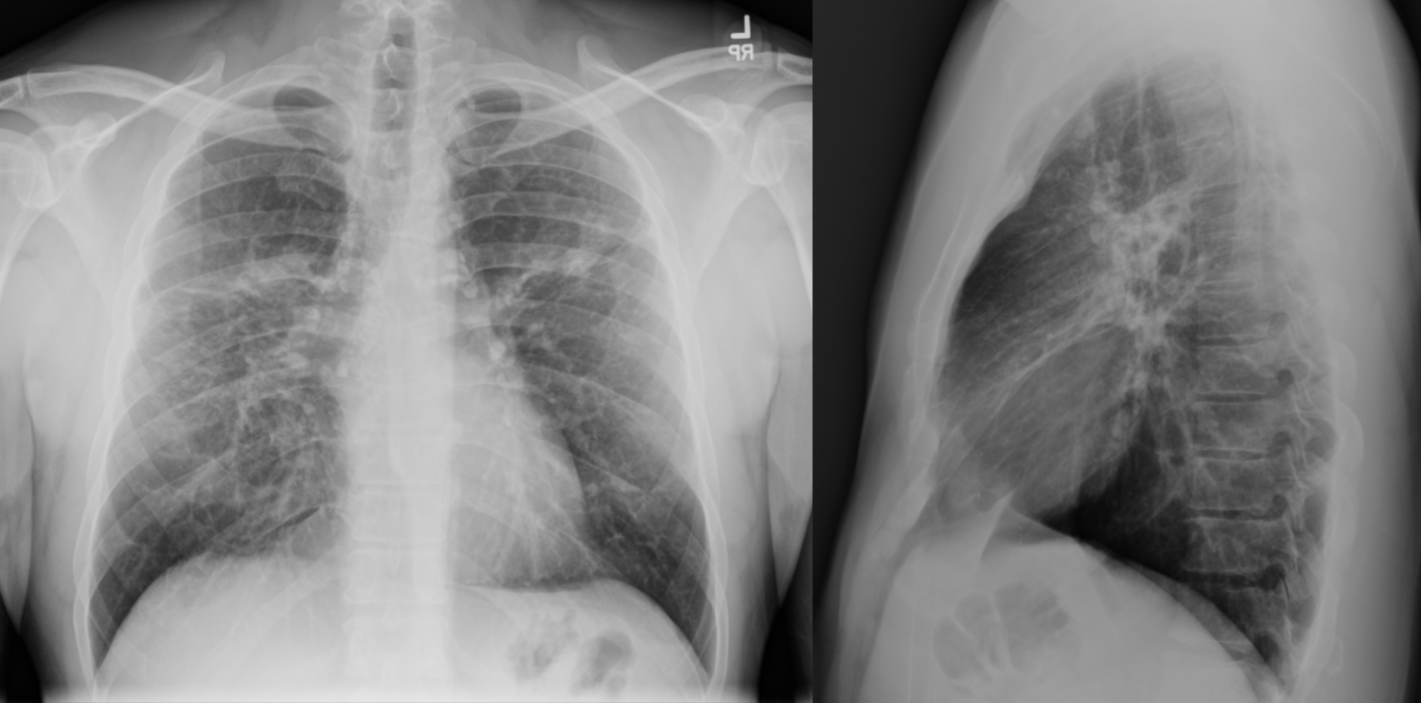

Identify this condition.

What is sarcoid?